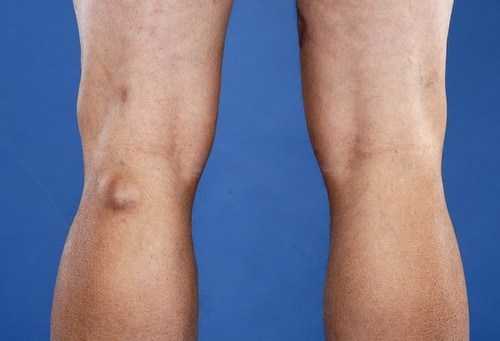

Киста Бейкера – это новообразование на задней поверхности колена. Она находится близко к коже, поэтому хорошо видна при осмотре. Внешне образование напоминает плотную шишку, при ощупывании подвижна, безболезненна. При сгибании и разгибании коленного сустава сопровождается дискомфортными ощущениями.

Киста на колене – внешний вид и симптоматика